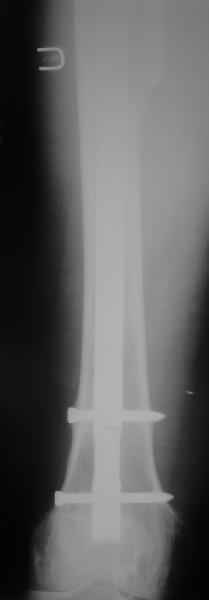

Сейчас опорную нагрузку на бедро берет на себя система от бедренного компонента эндопротеза до проксимального винта в интрамедуллярном гвозде. Свидетельство тому - реакция кортикала утолщением вокруг того самого винта. Таким образом вся кость от верхушки б.вертела до проксимального винта не испытывает физиологической осевой нагрузки. Результатом этого могут стать следующие последствия друг друга не исключающие: 1) все будет хорошо до перелома опорной системы по винту(ам) или в месте соединения штифта с ножкой или еще где-либо, 2) исключенная из-под нагрузки кость будет терять в количестве и качестве, что не очень (или очень не) хорошо для возможных будущих ревизий (тьфу-тьфу!!!).

Хотел бы обратить Ваше внимание, что реакция кортикала наблюдается только вокруг проксимального винта, дистальный винт не испытывает подобной нагрузки. Отсюда еще одна умозрительная авантюра - выкрутить только проксимальный винт. Изменения кости вокруг дистального винта тоже могут дать ответ на счет интеграции ножки, также как и появляется возможность сломать его. Страховаться (затратнее, но надежнее) или нет(легче, но не безопасно) динамическим винтом - на Ваш выбор.

О качестве сращения перелома тоже сказать трудно. Выраженной мозоли нет. В боковой проекции отломки накладываются друг на друга. В прямой проекции зона перелома в наружной части закрылась не полностью. Возможно причина тому - недогрузка кости.